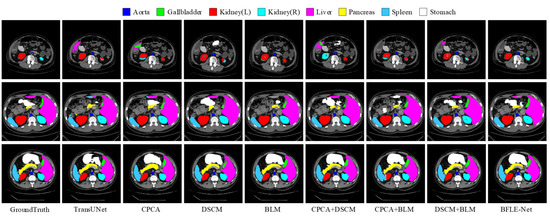

4.3.3. Ablation Experiment

To validate the effectiveness of the designed CPCA, BLM, and DSCM modules, a systematic ablation experiment was conducted. The performance contribution of each module to the overall model was quantitatively assessed by sequentially introducing each module. The detailed results of this analysis are presented in Table 5 and Figure 8 and Figure 9.

The experimental results reveal that the introduction of the CPCA module alone leads to an improvement of 2.17 percentage points in the average DSC and a reduction of 10.65 mm in HD95, enhancing the segmentation performance of small organs through shallow feature purification. The BLM module alone improves the average DSC by 1.81 percentage points and reduces HD95 by 7.74 mm. Its boundary optimization strategy effectively enhances the sharpness of the segmentation boundaries. The introduction of the DSCM module alone improves the average DSC by 0.62 percentage points and reduces HD95 by 0.13 mm, with its multi-scale feature calibration mechanism enhancing the model’s adaptability to the overall anatomical structure.

In terms of combined module effects, the combination of CPCA and BLM achieves an average DSC of 81.33%, indicating that the synergy between interference filtering, feature purity enhancement, and adaptive information supplementation strengthens boundary segmentation performance. The combination of BLM and DSCM results in an average DSC of 80.42%, with HD95 reduced to 25.16 mm, significantly enhancing the model’s performance through the synergy of multi-scale features and boundary optimization. This combination improves the model’s ability to capture both local and global features, as well as its robustness in segmentation tasks.

When combining CPCA and DSCM modules, the average DSC is slightly lower than that of CPCA alone but still higher than that of DSCM alone, with a significant decrease in HD95. This suggests a trade-off when combining the modules, playing a crucial role in further optimizing boundary errors and complementing the segmentation task. The experimental results show that as the model becomes more comprehensive and complete, it can focus more on important information while suppressing the representation of irrelevant features, thereby enhancing its ability to handle complex segmentation tasks. The synergistic effect of each module has significantly improved performance, demonstrating the overall model’s boundary retention and scale adaptability while maintaining segmentation accuracy, strengthening boundary prediction capabilities, and validating the effectiveness of this method.

Figure 8. Visualization results of ablation experiments on the Synapse dataset.

Electronics 14 03054 g008